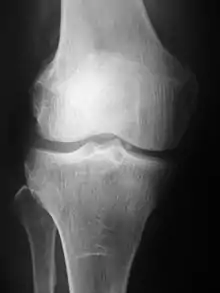

Projection (plain) radiography

Radiographs (originally called roentgenographs, named after the discoverer of X-rays, Wilhelm Conrad Röntgen) are produced by transmitting X-rays through a patient. The X-rays are projected through the body onto a detector; an image is formed based on which rays pass through (and are detected) versus those that are absorbed or scattered in the patient (and thus are not detected). Röntgen discovered X-rays on November 8, 1895, and received the first Nobel Prize in Physics for their discovery in 1901.

In film-screen radiography, an X-ray tube generates a beam of X-rays, which is aimed at the patient. The X-rays that pass through the patient are filtered through a device called a grid or X-ray filter, to reduce scatter, and strike an undeveloped film, which is held tightly to a screen of light-emitting phosphors in a light-tight cassette. The film is then developed chemically and an image appears on the film. Film-screen radiography is being replaced by phosphor plate radiography but more recently by digital radiography (DR) and the EOS imaging.[5] In the two latest systems, the X-rays strike sensors that converts the signals generated into digital information, which is transmitted and converted into an image displayed on a computer screen. In digital radiography the sensors shape a plate, but in the EOS system, which is a slot-scanning system, a linear sensor vertically scans the patient.

Plain radiography was the only imaging modality available during the first 50 years of radiology. Due to its availability, speed, and lower costs compared to other modalities, radiography is often the first-line test of choice in radiologic diagnosis. Also despite the large amount of data in CT scans, MR scans and other digital-based imaging, there are many disease entities in which the classic diagnosis is obtained by plain radiographs. Examples include various types of arthritis and pneumonia, bone tumors (especially benign bone tumors), fractures, congenital skeletal anomalies, and certain kidney stones.